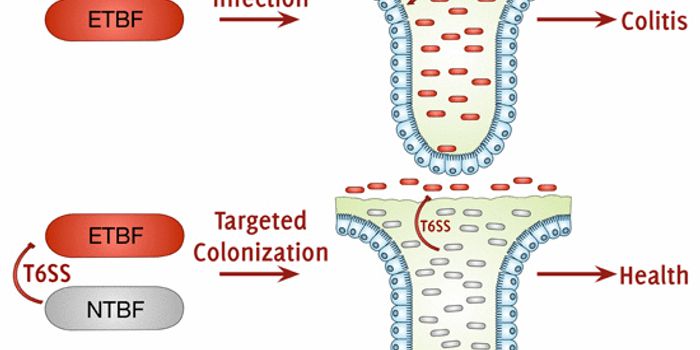

AUG 02, 2016MicrobiologyCommensal bacteria, the normal flora in the digestive tract, have a multitude of functions and are critical to health. O ...

AUG 18, 2019MicrobiologyThe world is full of bacteria that have to share the world with myriad species, and often have to live in competition wi ...

APR 15, 2015MicrobiologyIn recent years, research into the benefits of gut bacteria has exploded. Scientists across the globe are examining how ...